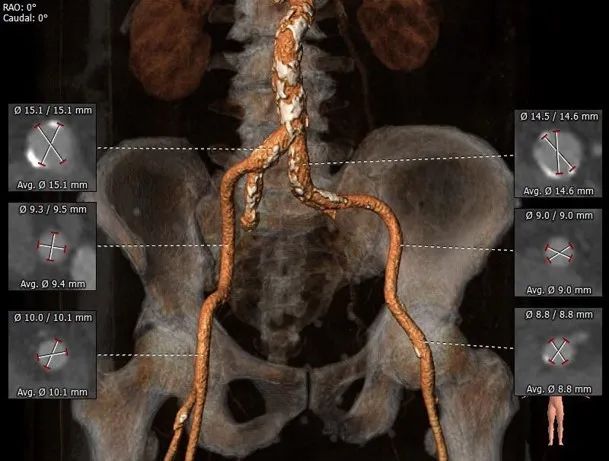

术前CT评估:

主动脉根部评估:

三叶式主动脉瓣,LVOT收口型,横位心。

入路评估:

外周血管内径可,走形适宜;主动脉弓宽度、夹角可。